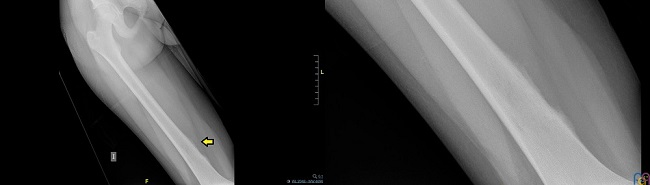

El triángulo de Codman es un signo radiológico, descrito por primera vez en 1926 por Ernest Amory Codman, que se observa con mayor frecuencia en las radiografías simples musculoesqueléticas e indica, en la mayoría de las ocasiones, la presencia de una lesión agresiva intraósea. Consiste en una reacción perióstica que ocurre cuando las lesiones óseas crecen de manera tan agresiva que levantan el periostio y no permiten que establezca hueso nuevo. Es un patrón de reacción perióstica interrumpida en la que el periostio se levanta en cualquier extremo de la lesión agresiva y el aspecto central de la lesión no tiene ninguna osificación suprayacente. Este estado da la apariencia en las radiografías simples de un triángulo elevado de periostio (Fig. 1) a lo largo de los bordes de la lesión. En esta reacción, el periostio puede levantarse por el borde delantero del tumor, pus o hemorragia1.

Se realiza una radiografía de fémur derecho, en la que se identifica en la vertiente posteromedial de la porción distal de la diáfisis femoral derecha la presencia de una reacción perióstica de características radiológicas agresivas (triángulo de Codman) (Fig. 1), así como una afectación esclerótica con dudoso patrón permeativo asociado en cortical ósea subyacente. Analítica y radiografía de tórax sin alteraciones.